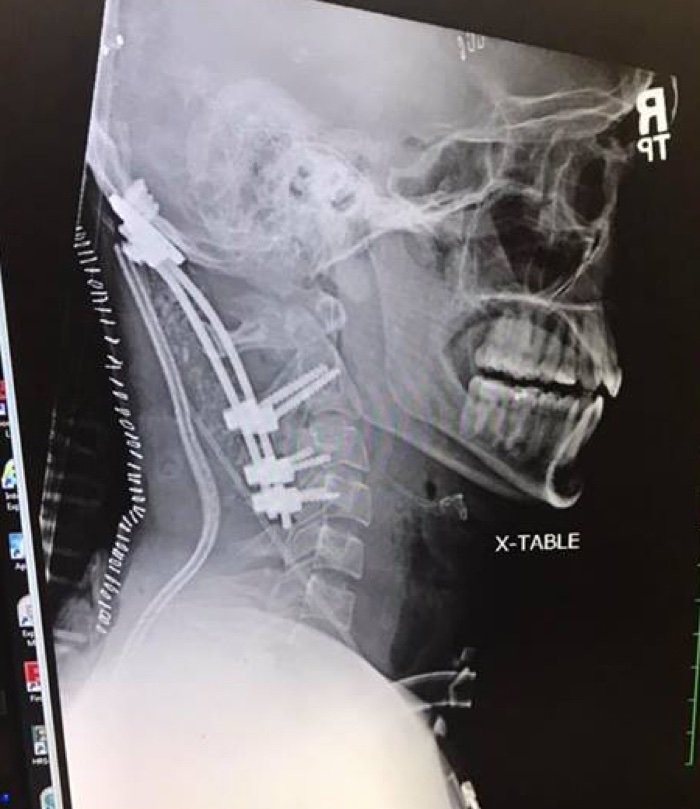

Приехавшие на место медики погрузили тело Мейстера на носилки и, вздыхая, уложили его в машину, говоря при этом: "Не жилец — внутреннее обезглавливание...". Это означало, что связки, прикрепляющие череп человека к позвоночнику, оторвались и голова держится только на коже.

"Когда связки в этой области разорваны, голова может двигаться больше, чем должна, что приводит к повреждению нижнего ствола мозга — жизненно важной области, контролирующей дыхание"

Тем не менее после того, как прошло критическое время, когда пациент уже должен был умереть, он всё ещё оставался жив. Было решено провести сложнейшую операцию. Хирурги сумели разместить в шее пластины, стержни и спинальные винты и стали надеяться, что всё это было не зря. Брук доказал, что не зря! Всё срослось, и постепенно Брук пошёл на поправку. Далее его ждал длительный курс реабилитации. Прошло 1,5 года, и парень уже может немного двигать шеей.